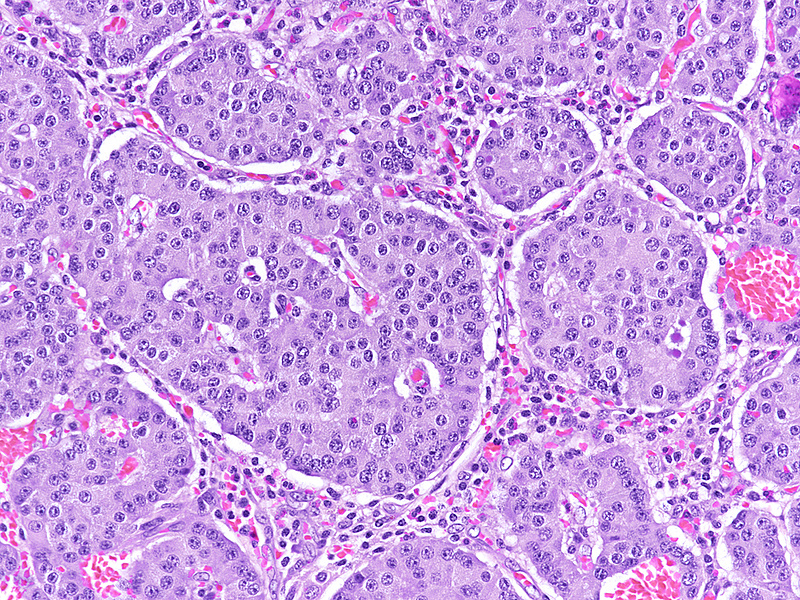

Upon magnetic resonance imaging (MRI) the pancreas contains several cystic lesions plus one partly solid, partly cystic lesion with a maximum diameter of 15 mm within the body. This lesion shows a biphasic pattern (Panel A). There are cysts lined by mucin-producing columnar cells with low grade dysplasia, consistent with a diagnosis of intraductal papillary mucinous neoplasm (IPMN). Other parts show a mainly solid, but also pseudoglandular growth of cuboidal cells with eosinophilic granular cytoplasm and centrally placed nuclei with “salt and pepper” chromatin and small nucleoli (Panels B-C). Mitoses are not detected. The two components merge with each other (Panel D), and in some foci the eosinophil granular cells underline the columnar cells (Panel E). The solid tumour component is strongly positive for synaptophysin (Panel F) and chromogranin A (Panel G), as are the underlining cells within the cystic component (Panel H). The Ki67 proliferation rate is low in the columnar epithelium (Panel I) and even lower (4%) in the solid component (Panel J). It is of note that the cells within the solid component express glucagon, while the cyst-lining mucus-producing cells are negative (Panels K-L).